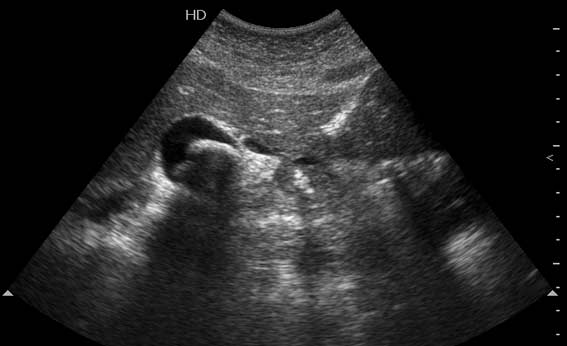

Мужчина 37 лет. Поступил в приемое отделение БСМП. Болен уже неделю, лечился в поликлинике. Сегодня боли усилились и стали нестерпимыми.

2 Между ж.пузырем и головкой панкреас -полый орган с отечными стенками-12 п.к.?(может быть сочетание язв.б-ни и ж.кам.б-ни)Если камень не в устье,то показана ФГС

Вы правильно разглядели пенетрирующую язву 12ПК. Перфорация прикрыта тканью печени, есть чуть-чуть свободной жидкости в ложе желчного пузыря. А ведь можно было "диагностировать" и острый холецистит!